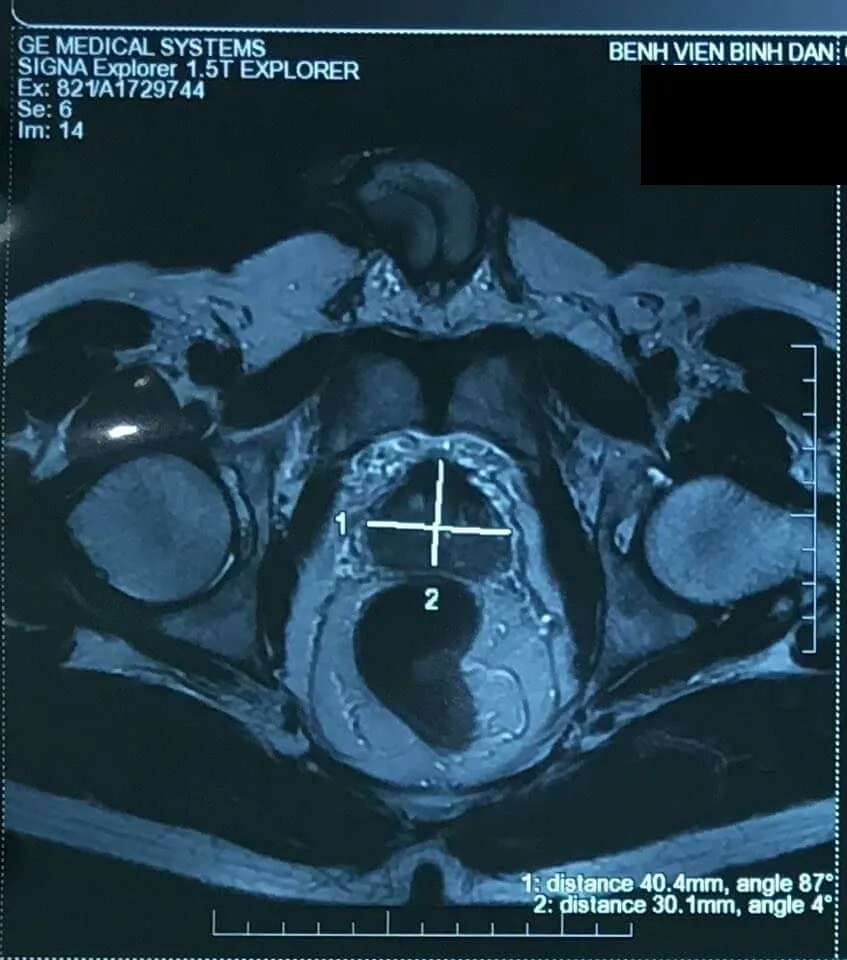

Trước đó, trong một đợt tầm soát sức khỏe vào tháng 10-2017, ông D. được các bác sĩ khoa Tiết niệu BV Bình Dân phát hiện bị ung thư tuyến tiền liệt. Ngoài ra, chụp cộng hưởng từ (MRI) cho thấy khối choán chỗ lan toàn vùng ngoại biên, chưa xâm lấn túi tinh hai bên, chưa xâm lấn vỏ bao. Kết quả xạ hình xương cũng chưa ghi nhận bất thường.

Hình ảnh khối u tiền liệt tuyến của ông D.